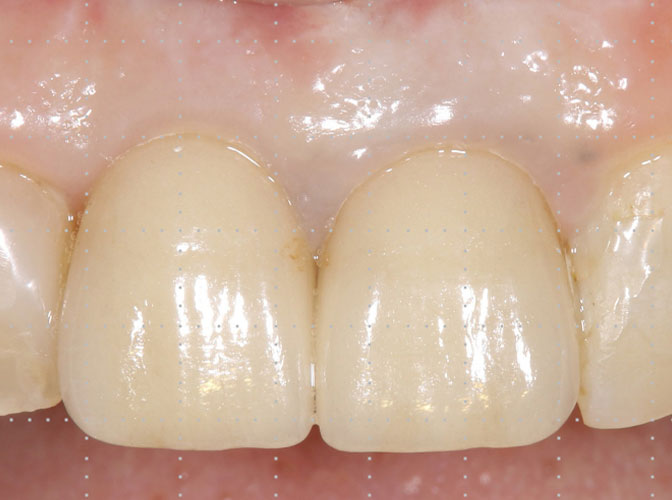

下の画像をご覧ください。これが、マイクロスコープで拡大した患部です。この機器を利用することで、再発や抜歯を回避できる確率が格段に高まりました。